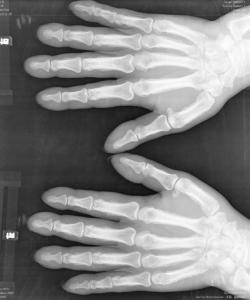

肥大性骨關節病患者完全沒有症狀,未意識到有杵狀指。在出現杵狀指之前即有明顯的慢性骨骼疼痛,以酸痛為主,部位較深,常不能明確指出具體部位,無法堅持工作。杵狀指為最突出的臨床表現之一,指(趾)端呈球狀正常的甲周160度角度減小,手指在甲床基部厚度超過遠端指間關節的厚度,甲床基部周徑大於遠端指間關節的周徑。由於甲床軟組織增生和水腫,指甲觸診有一種“擺動感”。晚期皮膚增厚,指甲變彎,發紺,產生鼓槌樣畸形。部分患者手足增粗變厚,長度不增加而呈鏟狀或獸掌狀。

(1)X線檢查主要的X線改變是程度不一的長骨及短骨對稱性骨膜新骨形成。